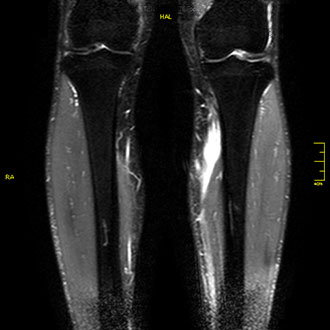

Die MRT der Arme und Beine dient der genauen Darstellung der Extremitätenmuskulatur – beispielsweise bei Muskelrissen, Blutungen, Sportverletzungen oder entzündlichen Veränderungen.

Ein klassisches Beispiel ist der Muskelriss oder die Blutung im Unterschenkel nach sportlicher Belastung.

Die MRT zeigt Ausdehnung, Lokalisation und Heilungszustand der Verletzung exakt und ist damit eine unverzichtbare Grundlage für die Therapieplanung.